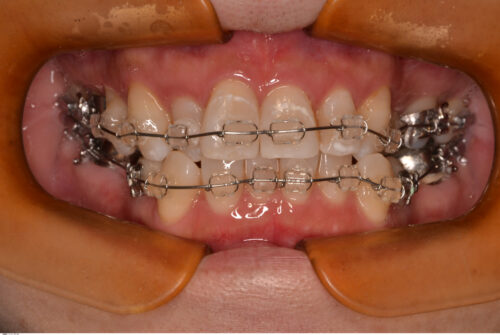

右上2番と左上3番が反対咬合のため、下顎のスムーズな側方運動が阻害されています。

矯正治療を開始します。